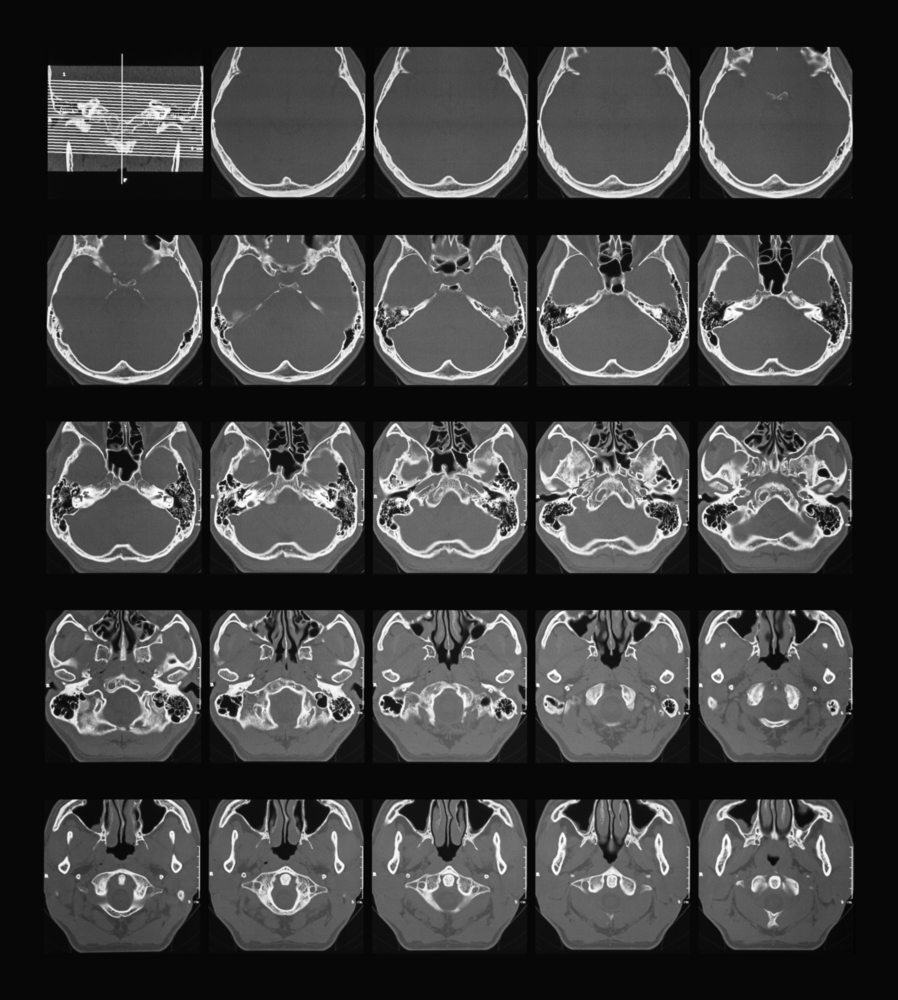

Аксиальная проекция

Во время диагностической процедуры пациент лежит на спине. Плоскость сканирования проходит через верхний край наружного слухового прохода и верхнюю стенку глазницы в краниальном направлении. Для сканирования используется компьютерная томография высокого разрешения с шагом 0,05-0,1-0,2 см и такой же толщиной среза.

Фронтальная проекция

Для проведения КТ в этой проекции пациент располагается лежа на животе или спине. С целью получения наиболее качественных изображений в момент сканирования ему рекомендуется задержать дыхание и не совершать глотательные движения.

Исследование начинается от передних отделов наружного слухового прохода и заканчивается у ложа сигмовидного синуса.